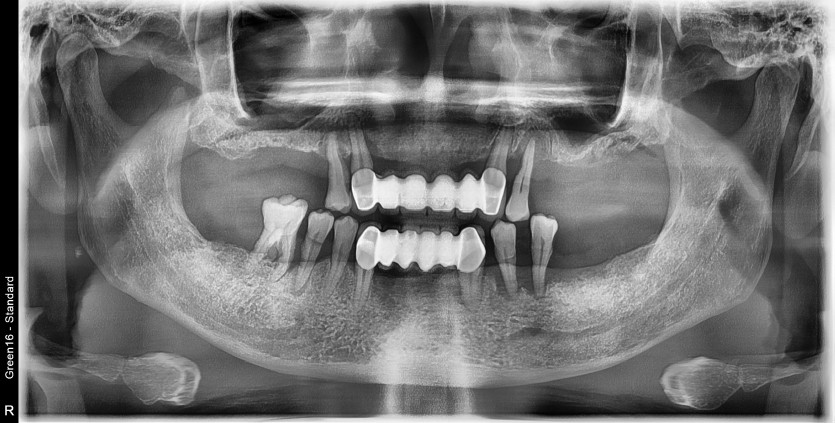

만 56세 상악 전체 임플란트 증례(하악 일부)

상악 전체 임플란트 증례입니다.(하악 일부)

15개의 임플란트로 완성하였습니다.